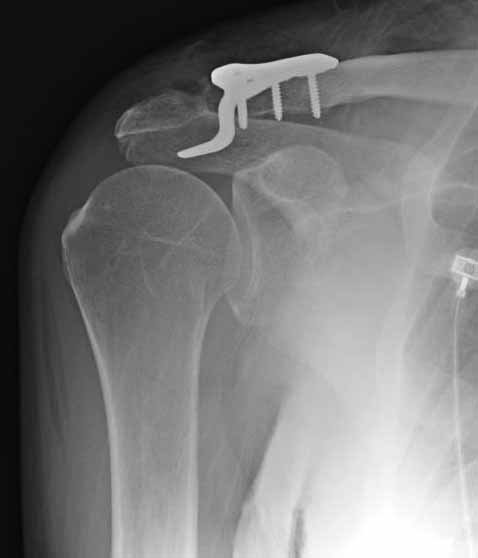

foto 3

3.JPG

14KB (15209 bytes)